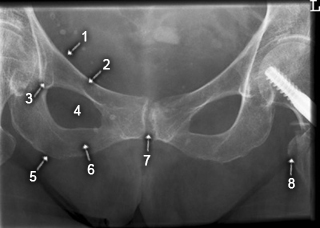

Symphyse

1. Linea terminalis

2. R. superior ossis pubis

3. Köhler-Tränenfigur

4. Foramen obturatum

5. Tuber ischiadicum

6. R. inferior ossis pubis

7. Symphysis

8. Trochanter minor